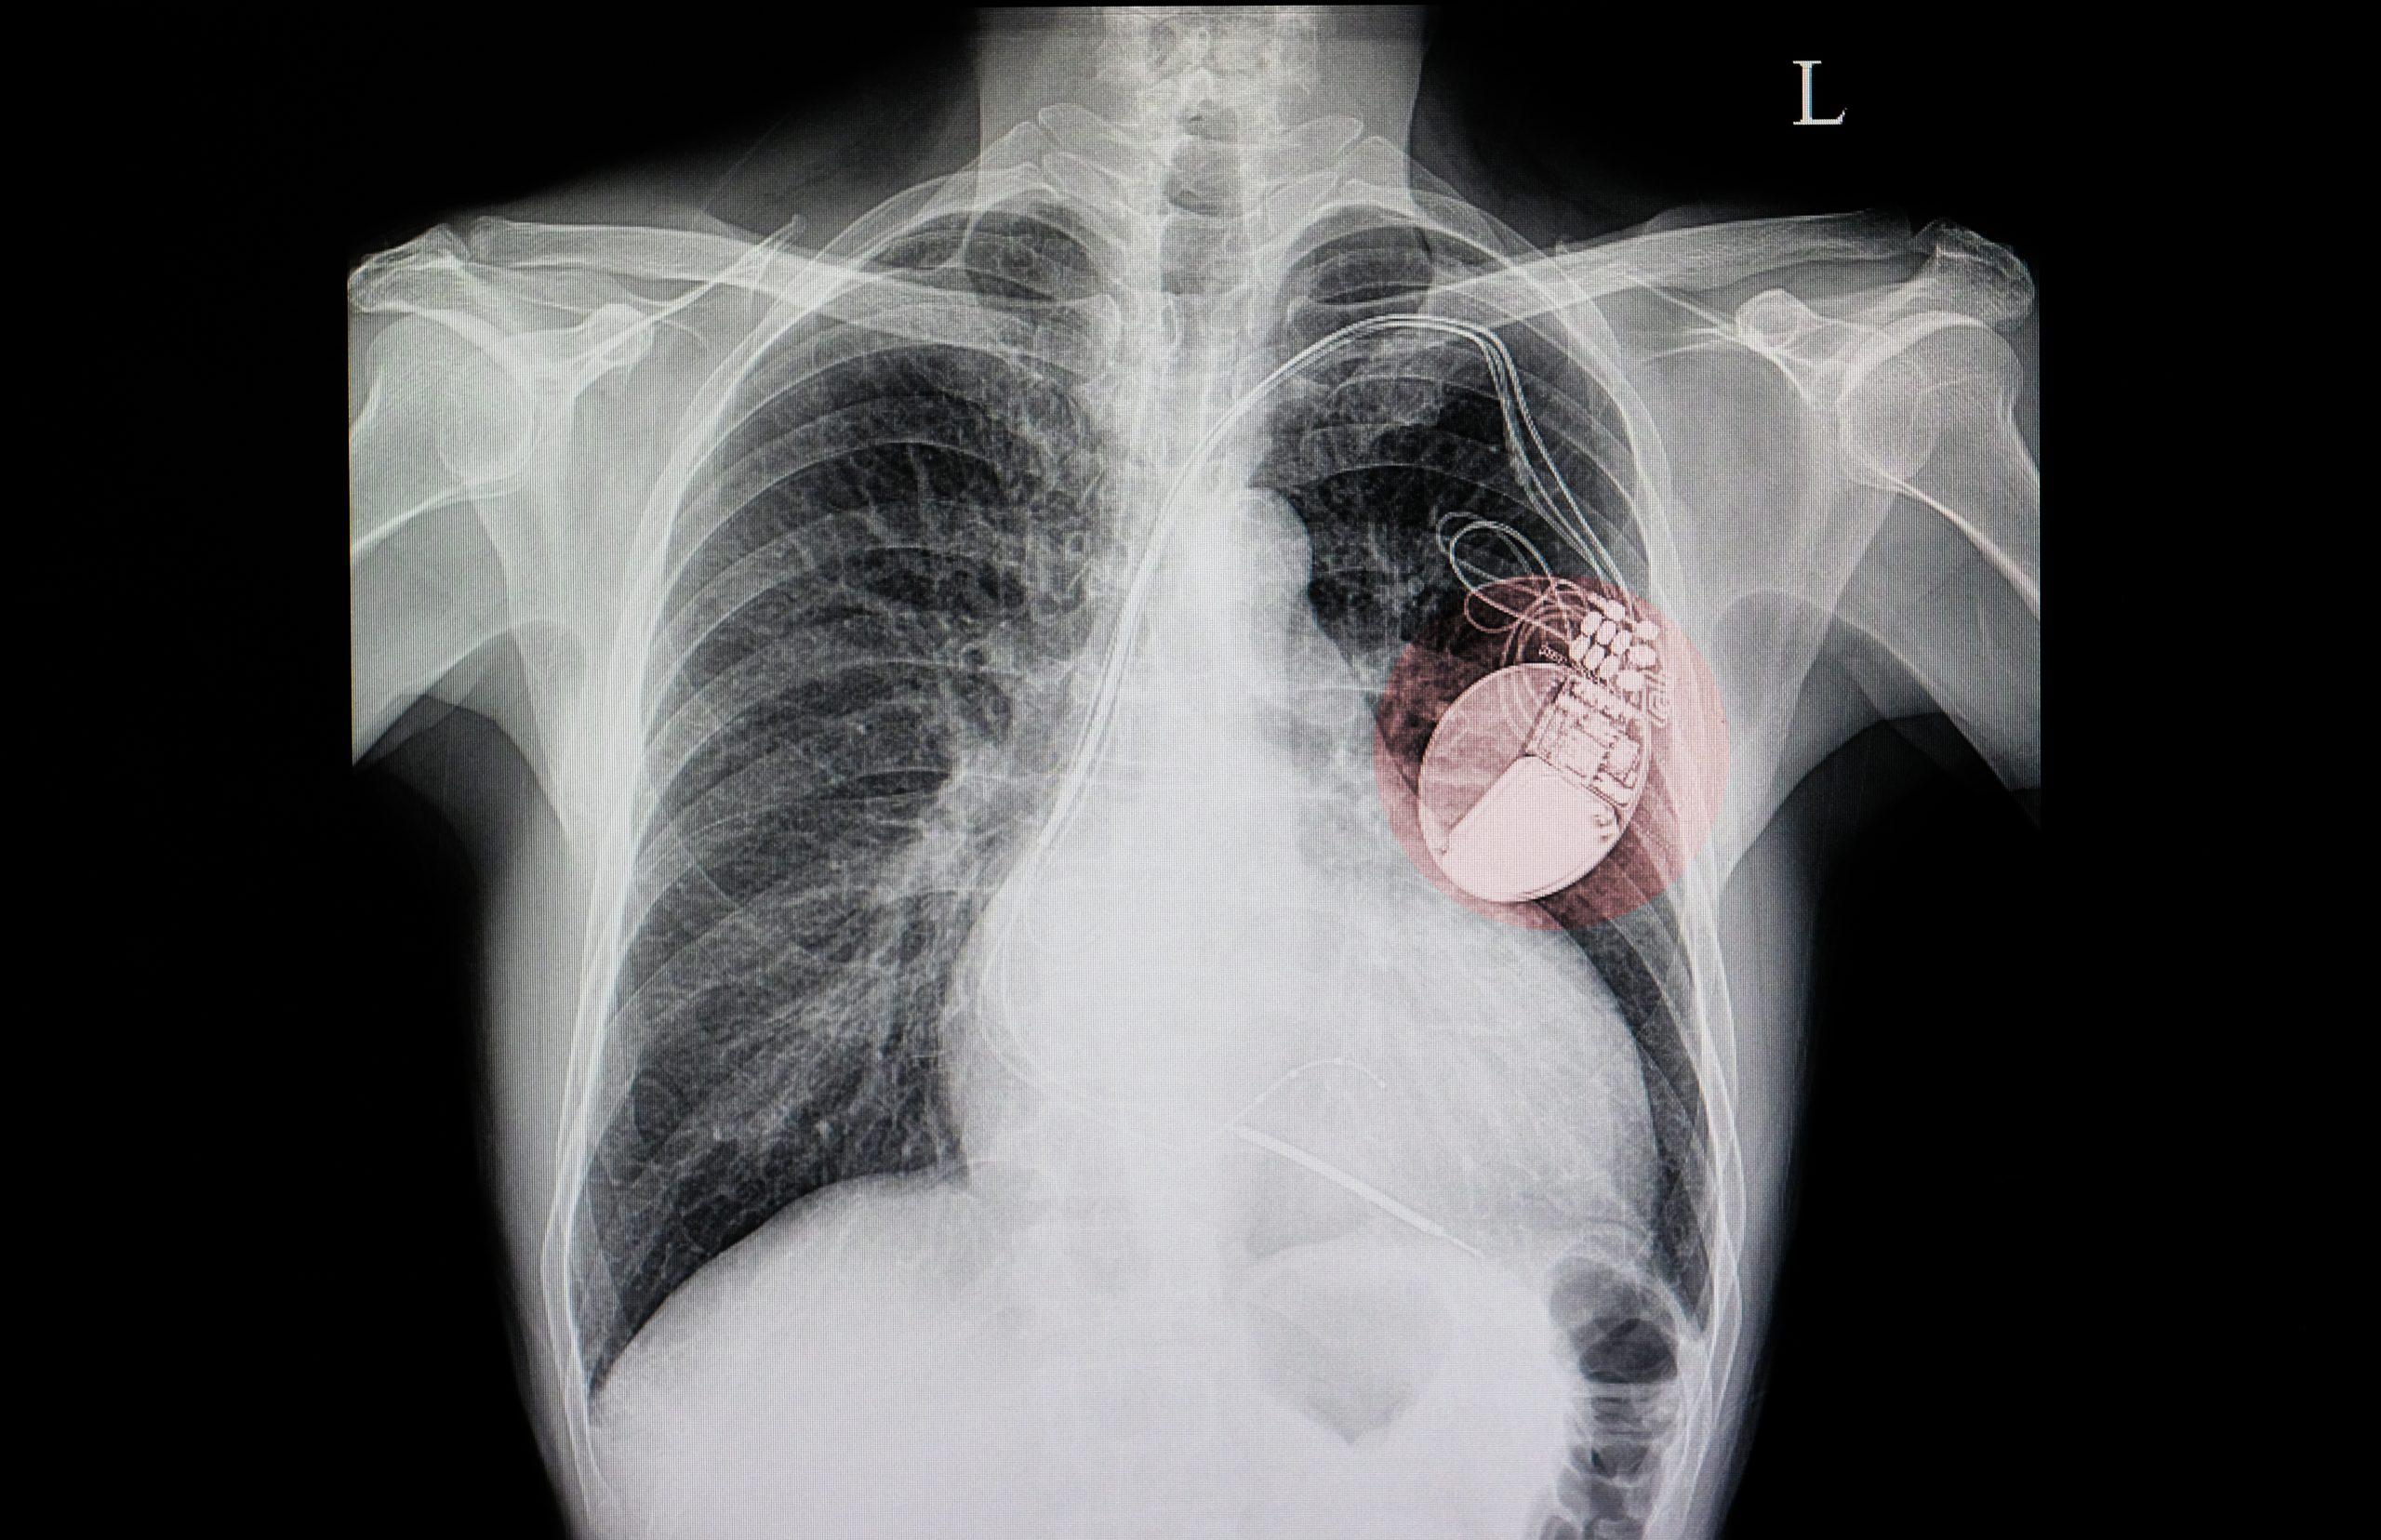

Dispositivos cardíacos eletrônicos implantáveis (DCEI), que inclui marca-passos e cardiodesfibriladores (CDI), são dispositivos de uso comum, com cerca de 1,5 milhão de implantes no mundo anualmente. …